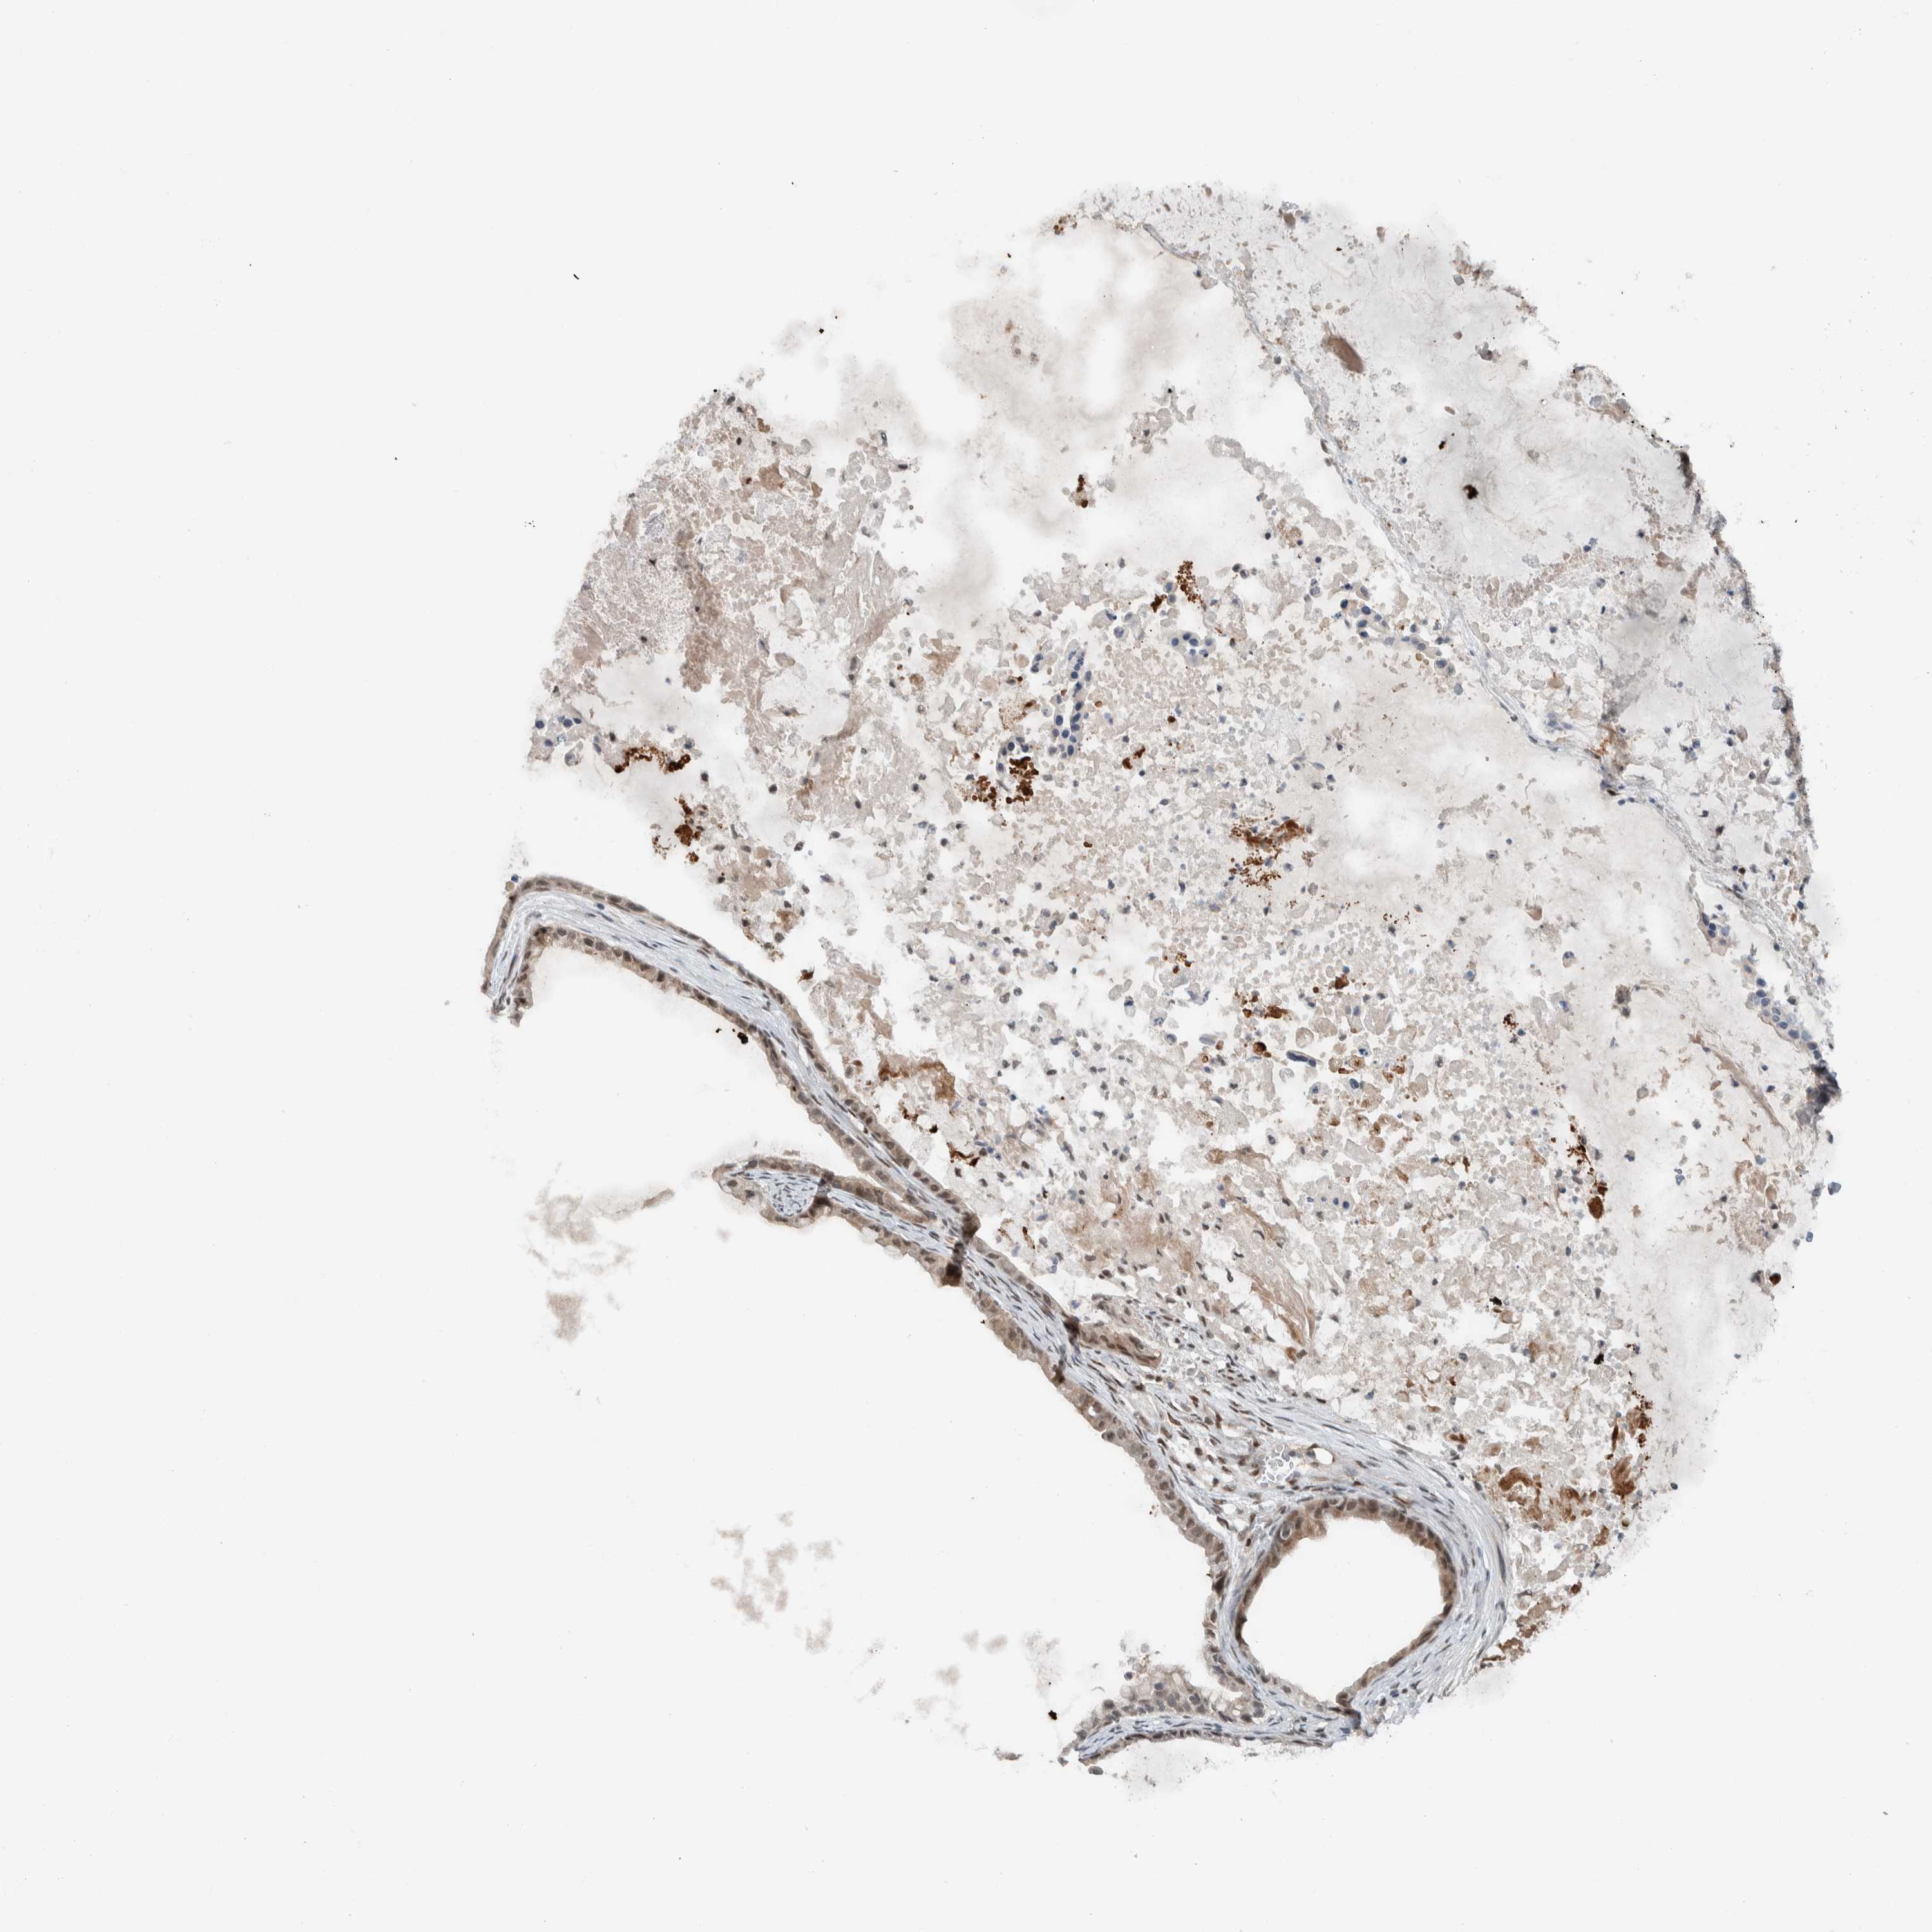

OVARIAN CANCER - Protein expressioni

A mouse-over function shows sample information and annotation data. Click on an image to view it in a full screen mode. Samples can be filtered based on level of antibody staining by selecting one or several of the following categories: high, medium, low and not detected. The assay and annotation is described here.

Note that samples used for immunohistochemistry by the Human Protein Atlas do not correspond to samples in the TCGA dataset.

Antibody stainingi

Antibody staining in the annotated cell types in the current human tissue is reported as not detected, low, medium, or high, based on conventional immunohistochemistry profiling in selected tissues. This score is based on the combination of the staining intensity and fraction of stained cells.

Each image is clickable and will lead to virtual microscopy that enables deeper exploration of all samples and also displays staining intensity scores, fraction scores and subcellular localization as well as patient and tissue information for each sample.

Antibody HPA024037

Antibody CAB025417

Cystadenocarcinoma, serous, NOS

Carcinoma, NOS